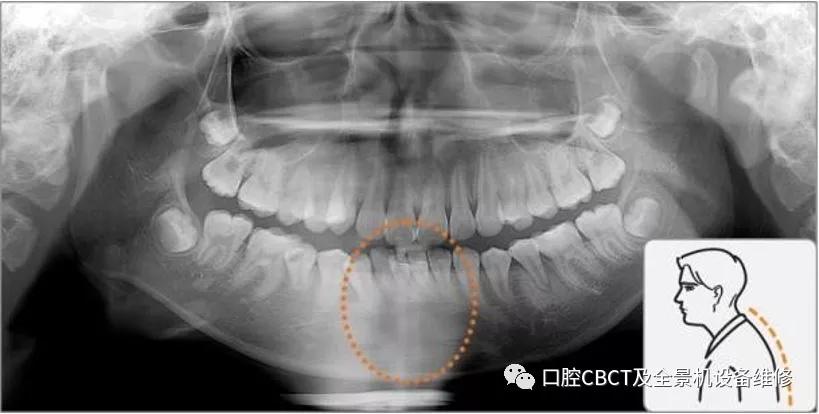

口腔全景x光机建议操作流程及注意事项

图片尺寸817x412

口腔全景机cbct拍片注意事项

图片尺寸819x414

图片尺寸867x438